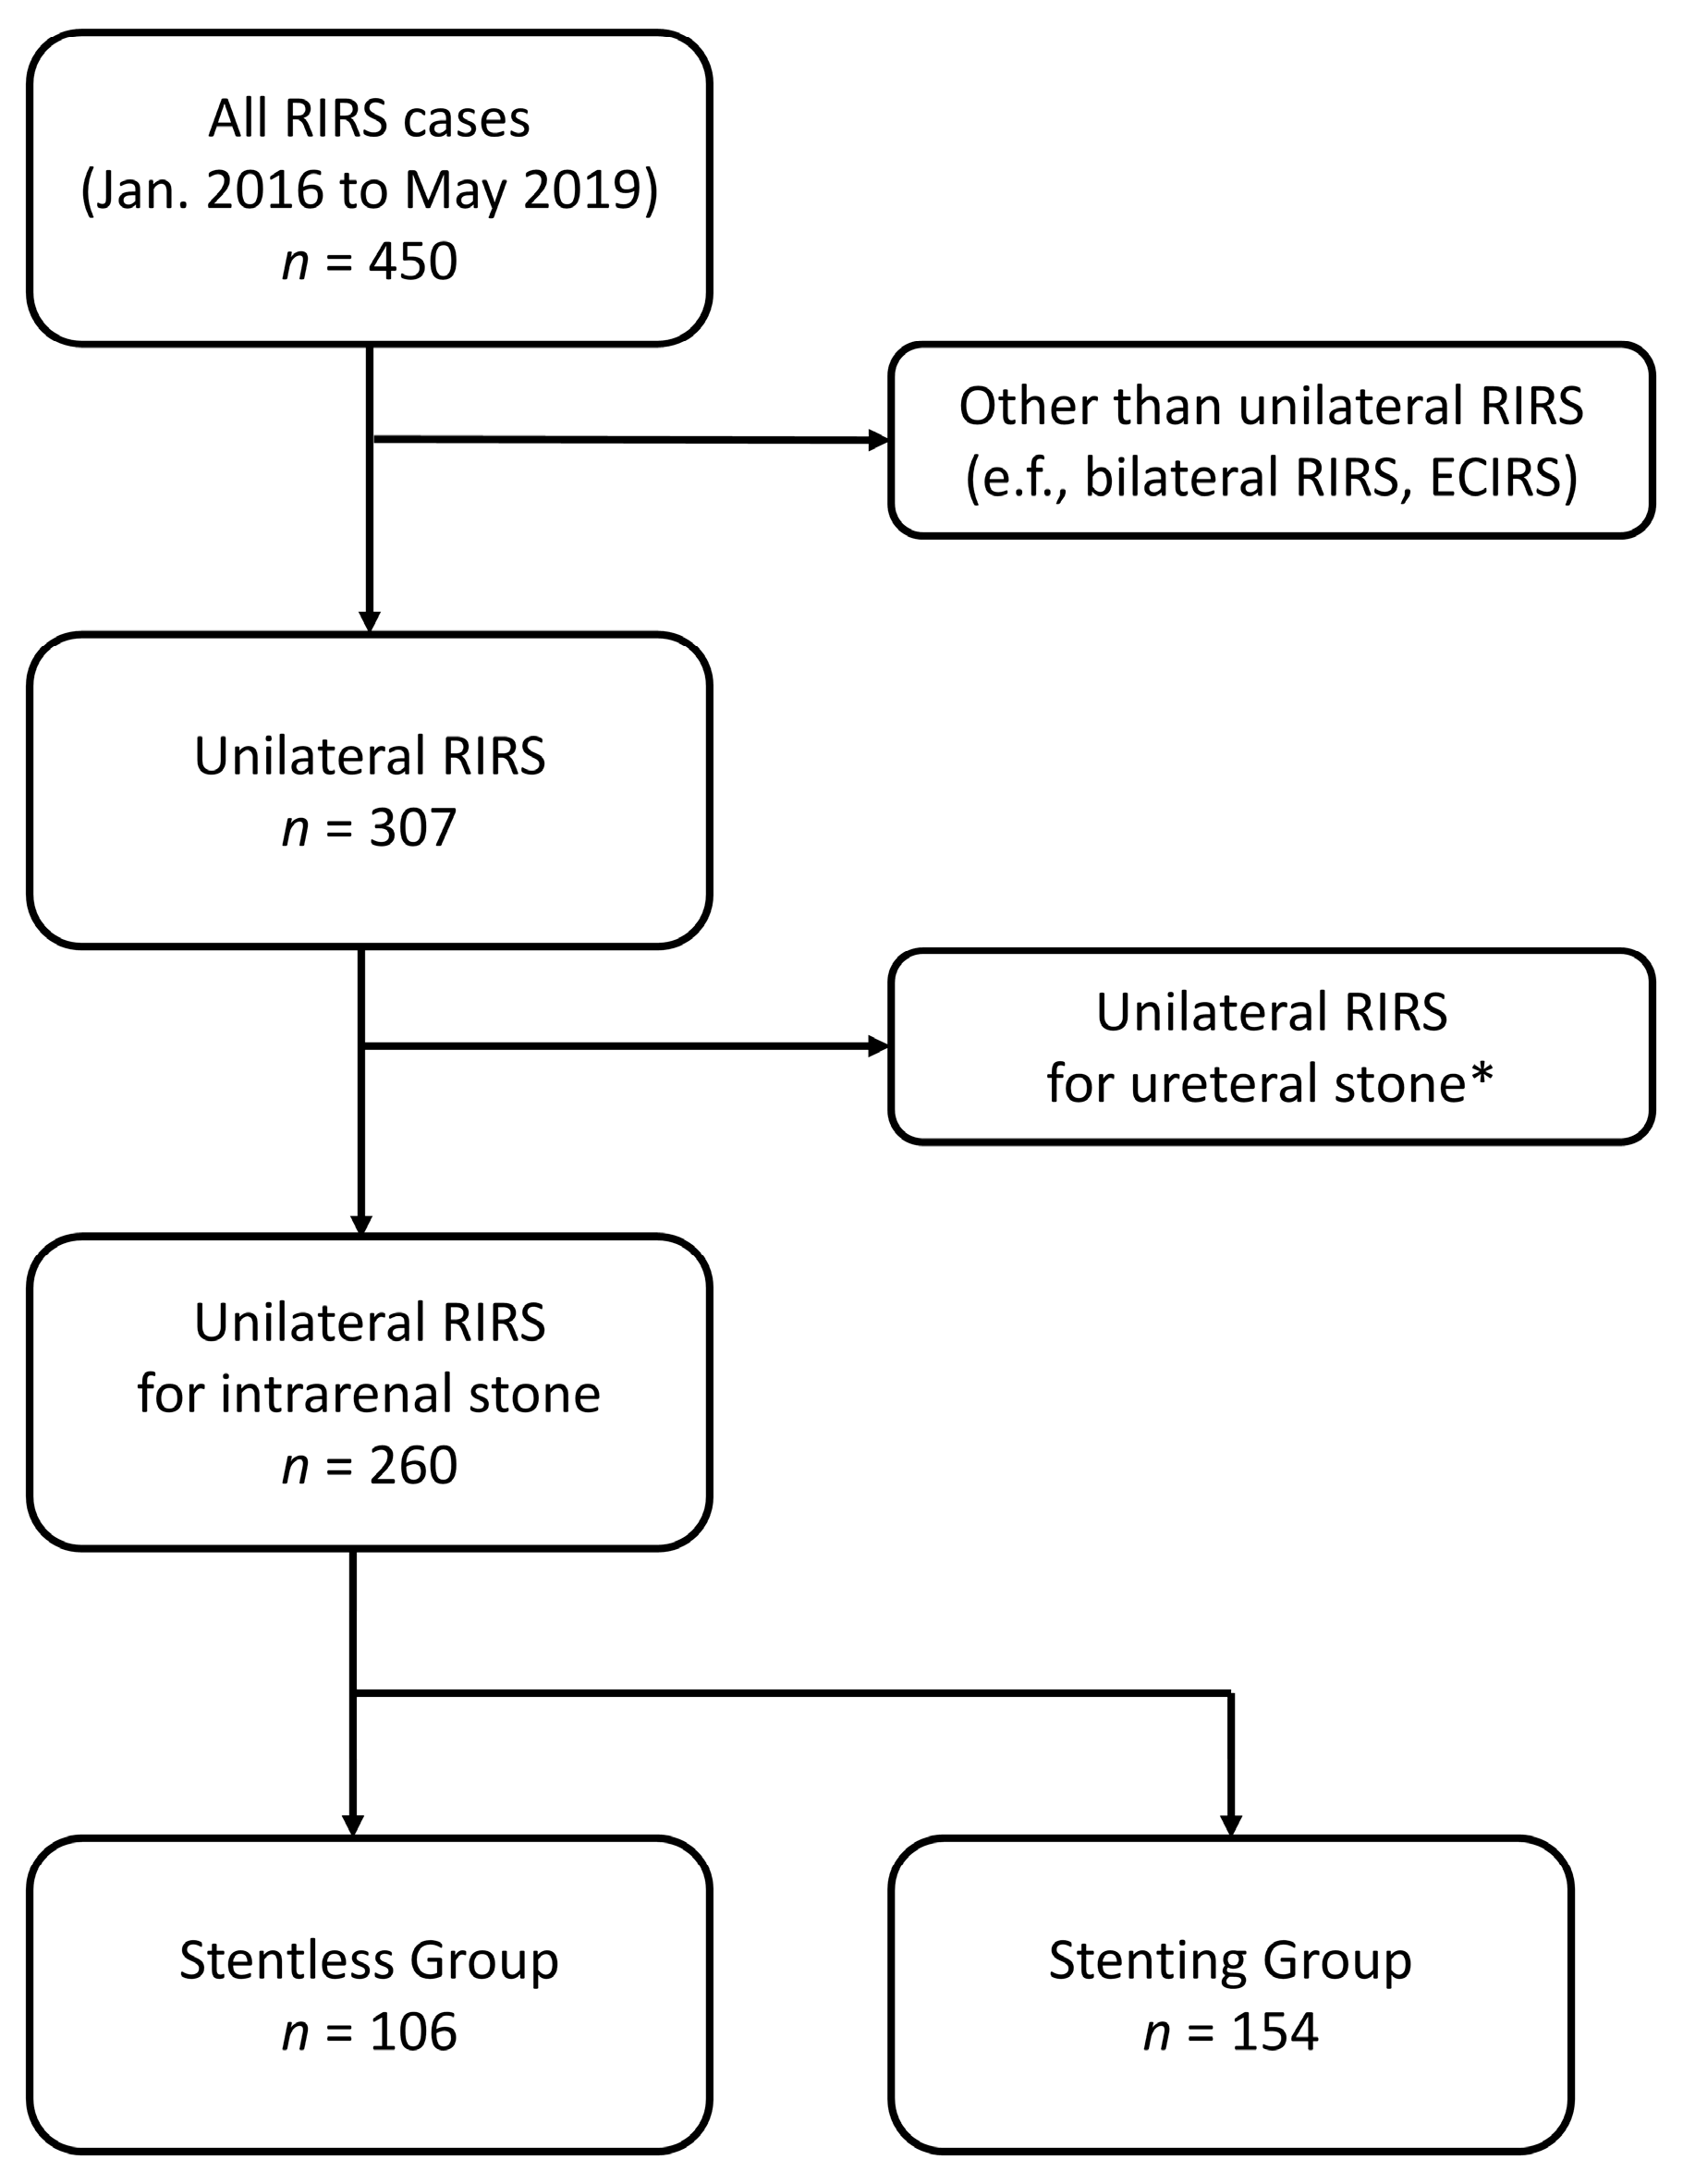

2.1. Study Population